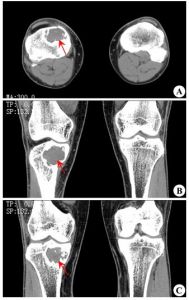

2、CT檢查軟組織惡性纖維組織細胞瘤CT圖像表現為密度均一的腫塊。骨內惡性纖維組織細胞瘤CT影像的差異較大,可以觀察到腫塊自骨破壞中心向四周組織中蔓延,多呈分葉狀,無完整包膜,軟組織腫塊有時巨大,呈低密度浸潤狀生長,邊緣不清,腫物中心常有壞死囊變區。

本組52例,男33例,女19例;年齡最大75歲,最小12歲,平均年齡48.7歲。病史3個月~5年,平均病史6.8個月。本組中BMFH主要以局部疼痛、腫脹及腫塊為主訴,主要發生於膝關節和肩關節周圍(分別32例和14例,約占88%),股骨近端3例,跟骨、腰椎、髂骨各1例。術前行X線片52例,CT49例,MRI48例。X線及CT以溶骨性骨質破壞為主,常伴有軟組織包塊,MRI清楚的顯示腫瘤侵犯的範圍。

患者,女,52歲,左脛骨BMFH。術前X線片及CT示脛骨斑片樣、蟲蝕狀骨破壞,周圍由硬化邊緣(略) MRI示腫瘤侵犯的範圍、軟組織包塊及周圍比鄰的關係(略)

BMFH由於缺乏特殊的影像學表現,故不能根據術前X線片、CT、MRI明確診斷,但影像學檢查可以幫助診斷,並且對確定手術方案有很大幫助。根據本組資料,作者總結BMFH影像學表現:(1)X線表現:BMFH的X線表現多種多樣,特徵性少。以蟲噬狀、斑片狀或大片狀溶骨性破壞為主,邊界不清,少數可有邊緣硬化,常伴有軟組織腫塊,骨膜反應無或輕微,這是BMFH的重要特點。(2)CT表現:更清楚地顯示骨質破壞和軟組織腫塊,骨質破壞同X線,少數病灶為囊狀或膨脹性,內有粗條索狀及格線狀嵴,並見邊緣硬化,類似良性病變,骨膜反應少見。(3)MRI表現:BMFH的MRI表現缺乏特異性,但其對腫瘤髓內侵犯、周圍邊界可清楚顯示,指導手術切除範圍,還可顯示腫瘤與鄰近血管的關係以及判斷腫瘤術後改變與術後復發等方面優於X線及CT。